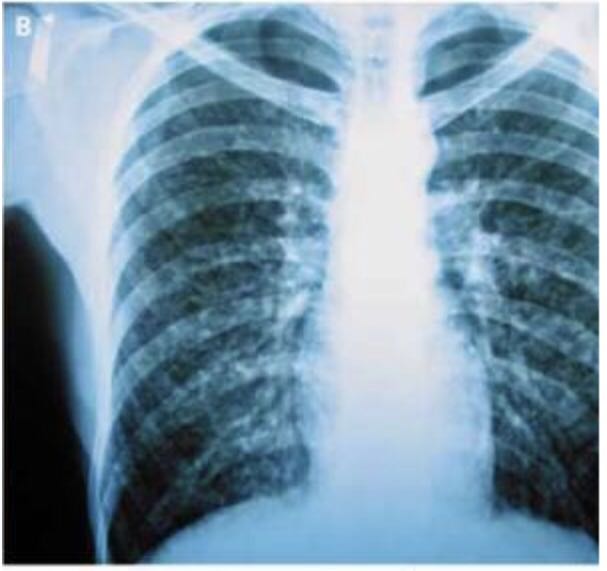

入院时胸片显示双肺多发小结节(图B)。无中枢神经系统或肝脏受累表现。